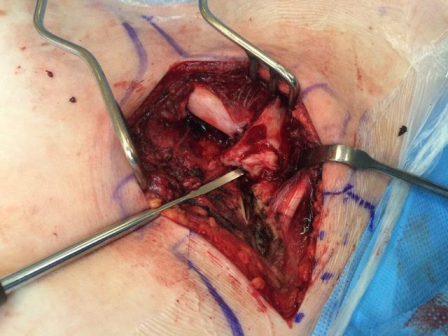

Fig. 4: Intra-operative image showing the rotated medial end of clavicle and disrupted sternoclavicular joint

The patient underwent emergency open reduction through a longitudinal incision along the medial clavicle. Surgical exploration showed the floating fragment, which was rotated and had a partially stripped periosteal sheath (Fig. 4); its medial end had a rough surface, and did not have the appearance of a cartilaginous articular surface, which corresponded to a fracture through the medial physis of the clavicle. Gentle manoeuvres were performed to reduce the fragment. Anatomic reduction and fixation of the lateral fracture with a reconstructive plate (which crossed only the lateral fracture) resulted in reduction of the fracture. Radiographic confirmation of the reduction was obtained and stability was tested with gentle mobilization of the ipsilateral upper extremity and loading of the SC joint. After surgery, the patient was placed in a sling for 4 weeks: progressive resumption of movements and activities was then allowed. After surgery the patient was asymptomatic; examination showed symmetry of the clavicles and of the SC joints, painless and complete range of motion of the left shoulder. Radiographs showed complete consolidation at three months (Fig. 5). The patient has resumed full activities and sports without problems subsequently.